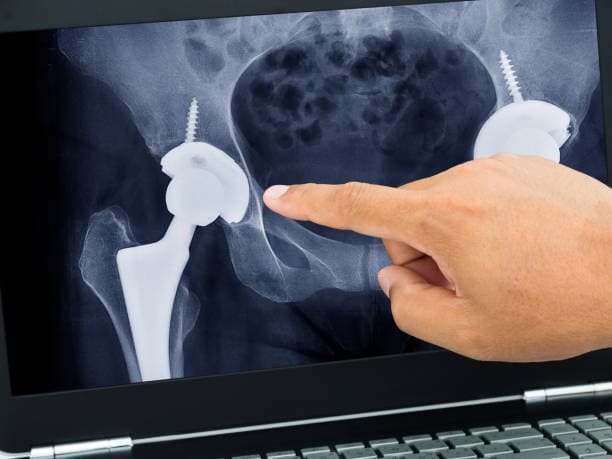

Preoperative Preparation: Before the surgery, patients undergo a comprehensive evaluation, including a review of their medical history, physical examination, and imaging studies such as X-rays or MRI scans. This helps the surgeon assess the extent of joint damage and plan the surgical approach. Patients are also advised to follow specific preoperative instructions, which may include discontinuing certain medications, fasting, and arranging for postoperative care and assistance.

Implant Placement: The prepared bone surfaces are fitted with the prosthetic components. The femoral component, which includes a metal stem and a ball, is inserted into the femur. This can be cemented in place or designed to allow bone growth into the implant. The acetabular component, typically a metal shell with a plastic or ceramic liner, is placed into the prepared socket. These components are aligned to ensure proper joint movement and stability.